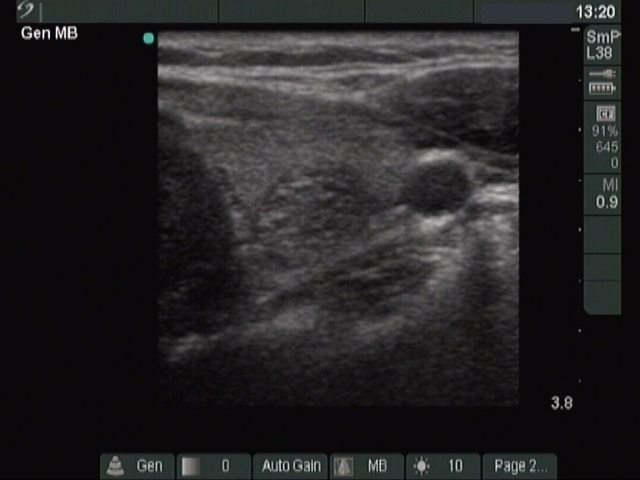

Ultrasonography: a moderately hypoechogenic nodule in the right lobe.